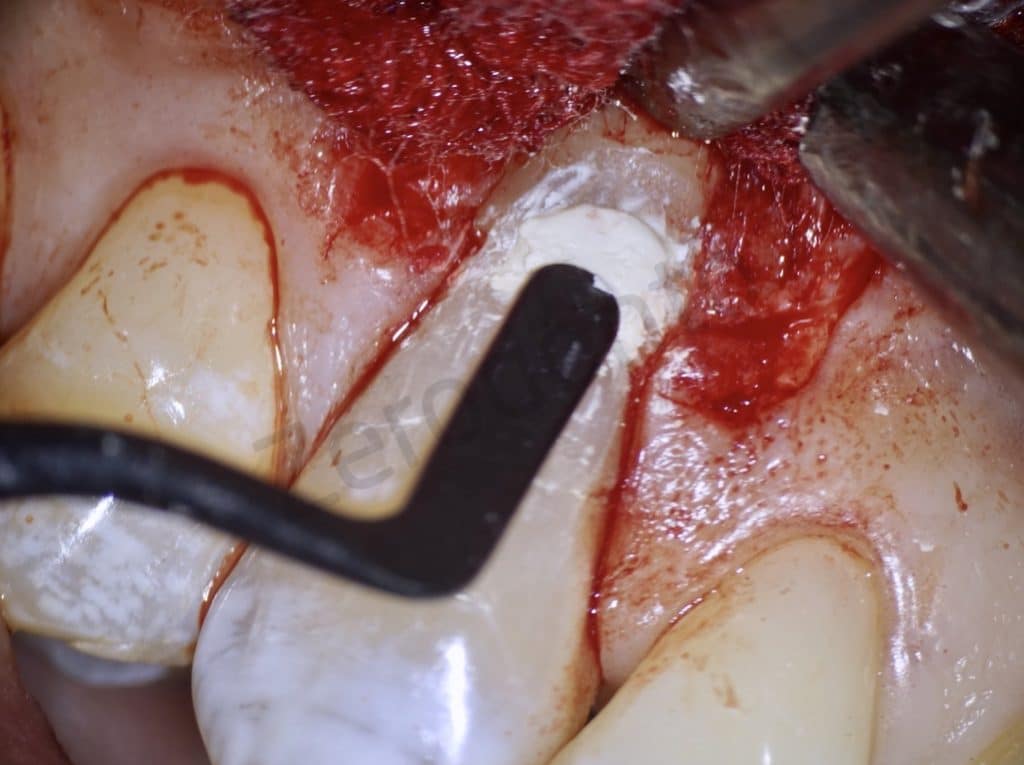

A coronal repositioning flap first at partial thickness then total thickness and finally a periosteal incision to mobilize the flap were performed. The anatomical papillae were disepithelized to allow the sliding of the surgical papillae.

After removing the granulation tissue as far as possible compatibly with maintaining the vitality of the tooth, the cavity was filled with Biodentine, a bioceramic, perfectly biocompatible cement based on synthetic tricalcium silicate which is a valid substitute for dentine itself. The control is at one year.

Flap

The lesion

Detail of the lesion

Restoring the lesion with Biodentine

Biodentine application